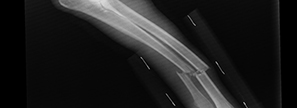

Adriana Andrade, paulista de 19 ans est arrivée aux urgences après avoir englouti son téléphone mobile. Tentative de record ? Non, Adriana souhaitait juste préserver son intimité.

Adriana n’est pas en danger mais elle doit rester quelques jours en observation à l’hôpital. Le modèle du téléphone « victime » n’a pas été communiqué, il s’agit probablement d’un téléphone de petite taille. Et la petite histoire ne dit pas le contenu des textos à l’origine de tout !